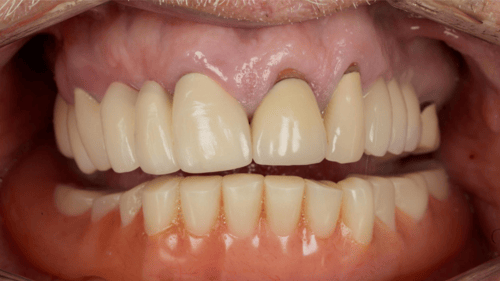

The patient presented with a history of dental implants in the maxillary and mandibular arches. The remaining maxillary dentition exhibited failure, chronic infection, and inflammation.

Preoperative radiograph Patient pre-op, retracted

A digitally driven treatment plan integrated existing implants with newly placed fixtures to support a fixed, implant-supported FP1 prosthesis. All diagnostics—including CBCT, intraoral scans, and patient photography — were digitally captured and approved before surgery.